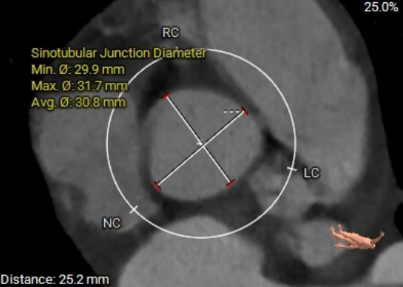

窦管交界:30.8mm

术前主动脉CTA评估:主动脉瓣二叶式type1型,L-R融合,瓣叶增厚、黏连,瓣叶游离缘、根部及融合脊中-重度钙化;主动脉瓣环周长折算直径约25.2mm;双侧冠脉开口高度可;双冠分支轻度钙化;术中建议造影角度LAO:9°,CRA:11°;左室流出道稍凸出;主动脉弓及降主动脉多发钙化,腹主动脉重度钙化。

瓣环:25.2mm

窦管交界:28.7mm